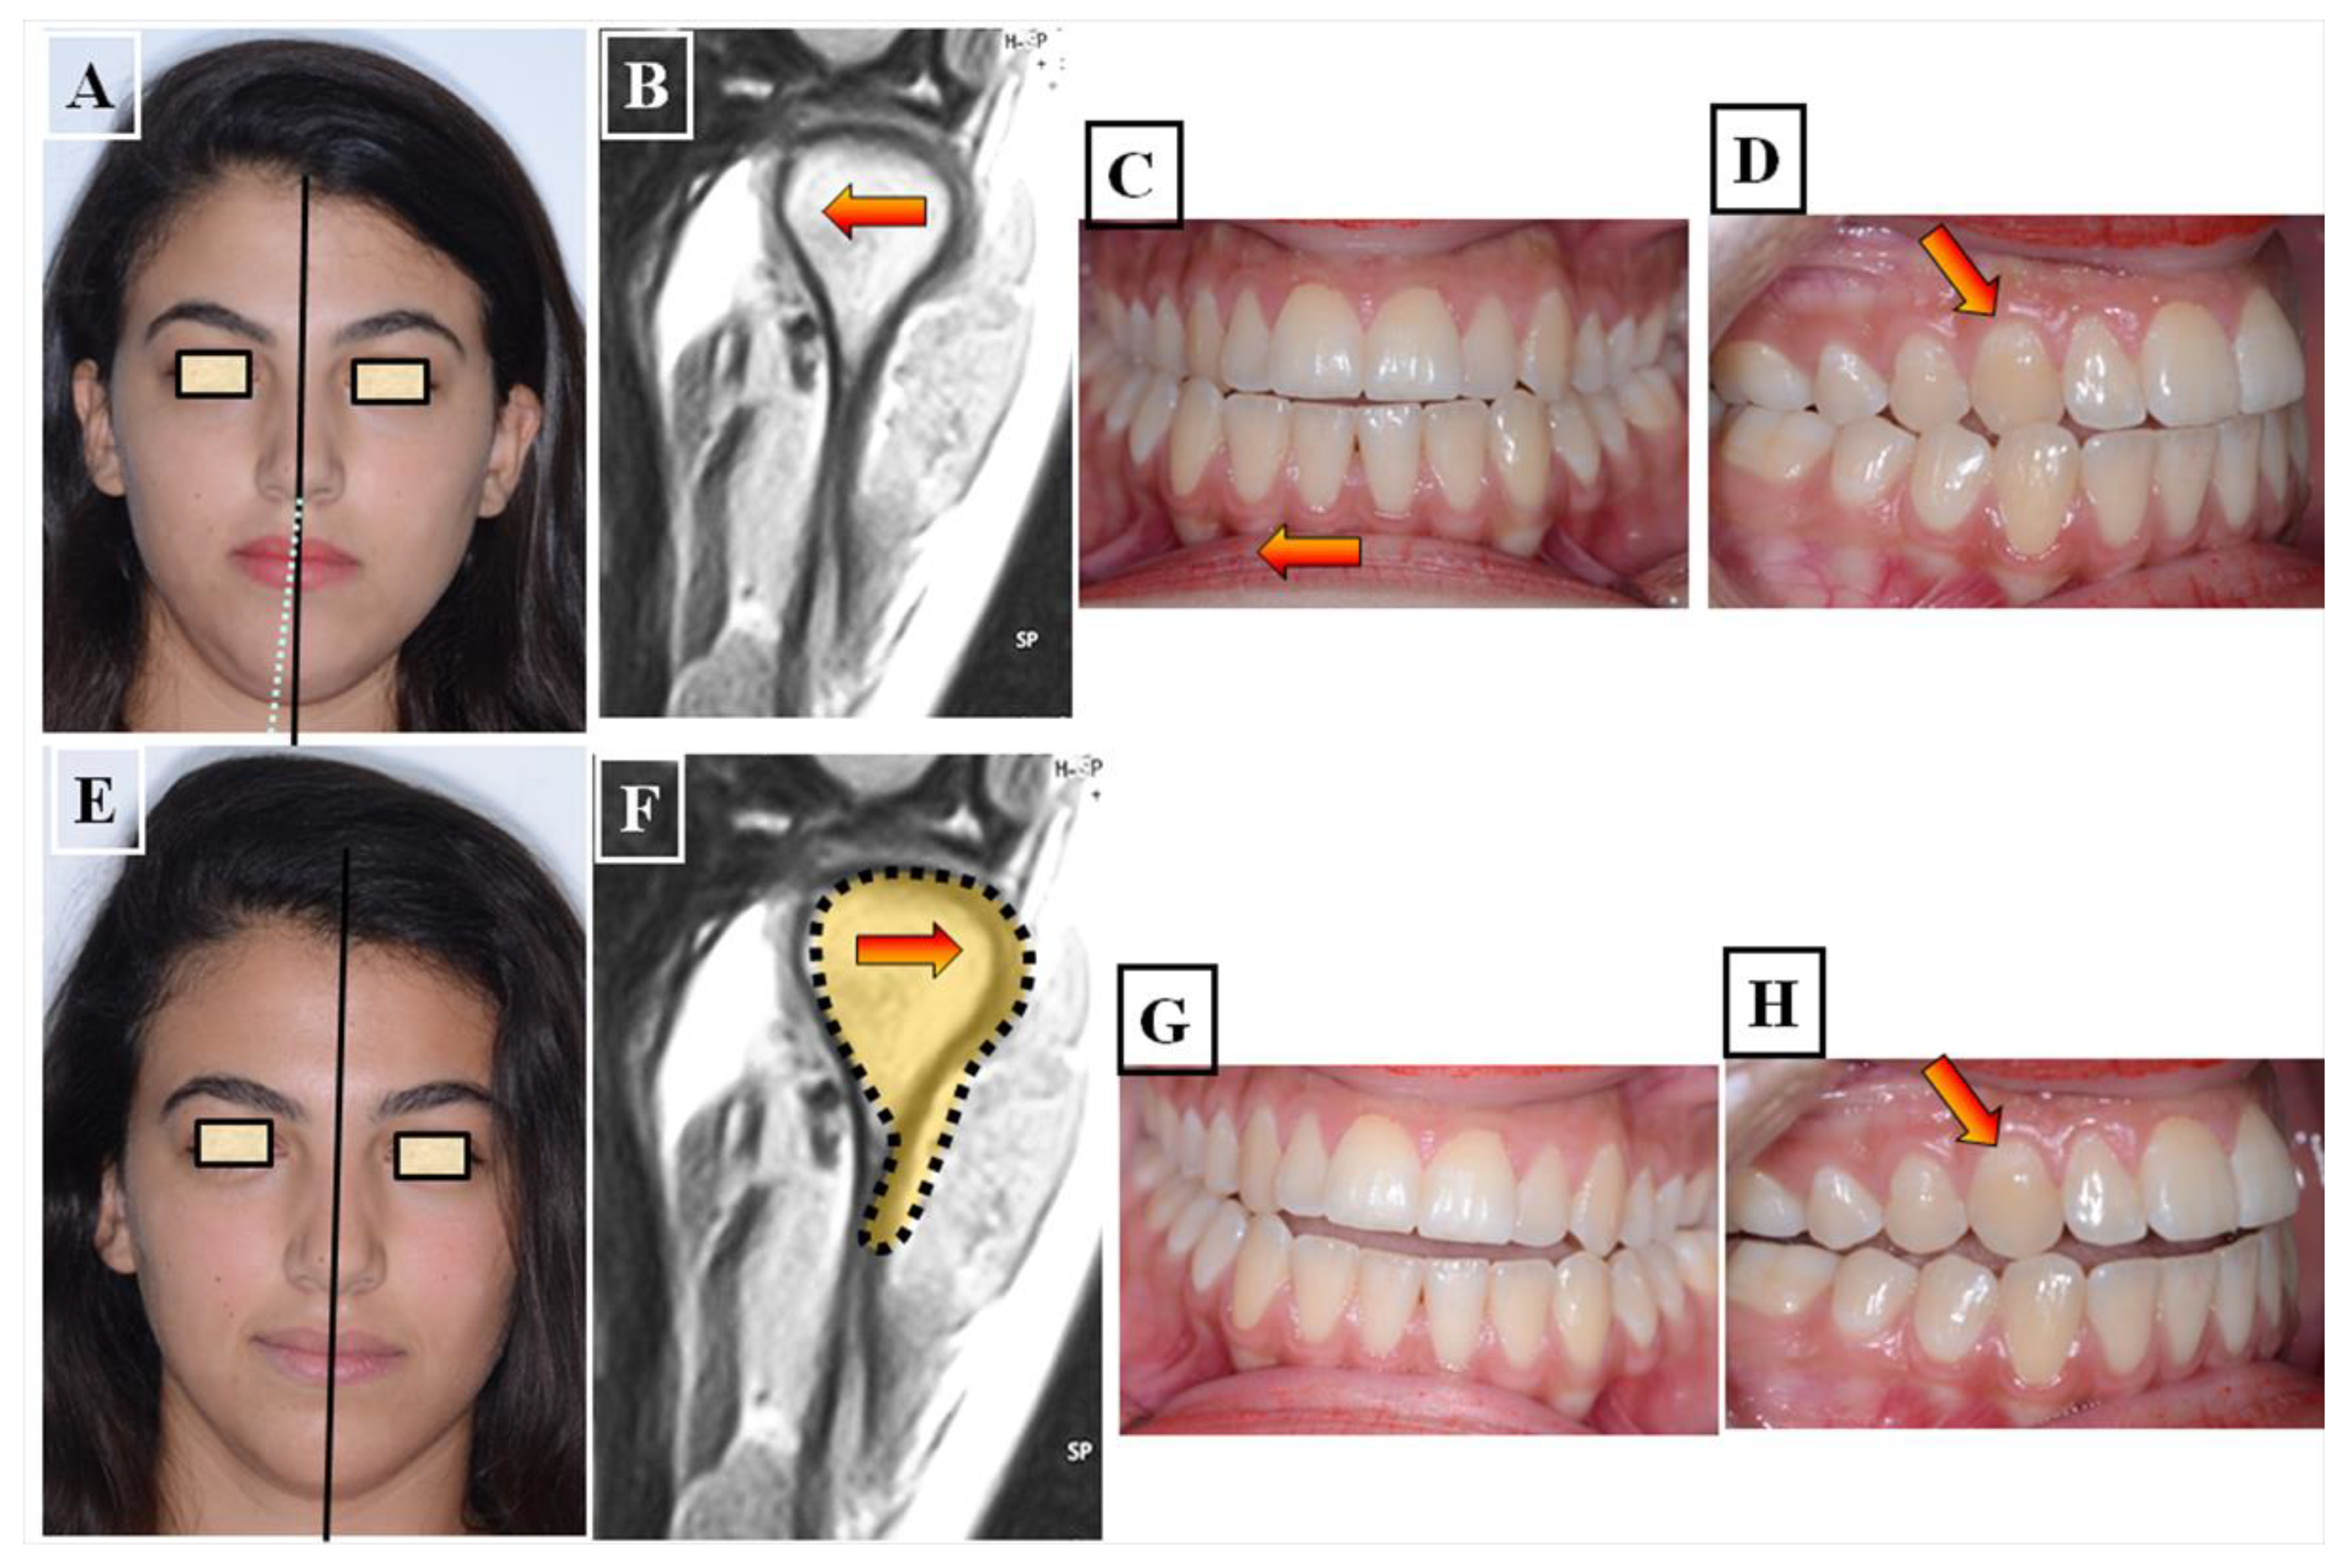

In this situation, two different occlusions with two different condyle positions can be observed—a habitual occlusion with a habitual condyle position and a centric occlusion with a centric condyle position. Typically, facial asymmetry is observed in habitual occlusion or the habitual condyle position. Manual functional analysis can achieve the centric condyle position with the corresponding change in occlusion. This helps reduce or completely eliminate facial asymmetry. A dentoalveolar malalignment is often involved in most cases (Figure 8A–H).

Figure 8.

Determination of the centric condyle position and thus centric occlusion after using a flat occlusal splint for decoupling the occlusion for 2–3 weeks. Situation before treatment and before using the occlusal splint, (A–D). Forced bite with crossbite to the right in the area of the canines 13 and 43 (arrow) with facial asymmetry to the right (white dashed line), habitual condyle position with habitual occlusion (The forced bite direction resulted in a change in position of the condyles (red arrow). The status of the patient after 3 weeks of using the occlusal splint. The forced bite has been eliminated, Instead of a crossbite on the canines, there is an edge-to-edge bite (red arrow). There is no facial asymmetry in the centric condyle position, the centralization of the condyles resulted in a new position of the condyles (red arrow) (E–H).